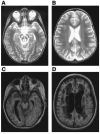

NADH:ubiquinone oxidoreductase (complex I) deficiency is a common cause of mitochondrial oxidative phosphorylation disease. It is associated with a wide range of clinical phenotypes in infants, including Leigh syndrome, cardiomyopathy, and encephalomyopathy. In at least half of patients, enzyme deficiency results from a failure to assemble the holoenzyme complex; however, the molecular chaperones required for assembly of the mammalian enzyme remain unknown. Using whole genome subtraction of yeasts with and without a complex I to generate candidate assembly factors, we identified a paralogue (B17.2L) of the B17.2 structural subunit. We found a null mutation in B17.2L in a patient with a progressive encephalopathy and showed that the associated complex I assembly defect could be completely rescued by retroviral expression of B17.2L in patient fibroblasts. An anti-B17.2L antibody did not associate with the holoenzyme complex but specifically recognized an 830-kDa subassembly in several patients with complex I assembly defects and coimmunoprecipitated a subset of complex I structural subunits from normal human heart mitochondria. These results demonstrate that B17.2L is a bona fide molecular chaperone that is essential for the assembly of complex I and for the normal function of the nervous system.